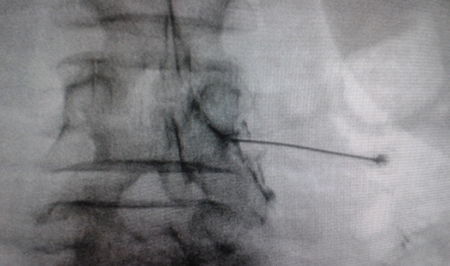

El acceso por vía transforaminal es el más utilizado (4). Se coloca al paciente en decúbito prono con una almohada a nivel abdominal para revertir la lordosis fisiológica. Las agujas o cánulas de radiofrecuencia que utilizamos con más frecuencia son de diámetro 20 o 22 G de 98 mm de largo con punta activa de 0,5 o 1 cm. Después de la asepsia con clorhexidina alcohólica y la colocación de campos estériles, se realizan enfoques radiológicos en incidencia anteroposterior, oblicuo y lateral. En incidencia anteroposterior y moviendo el arco en dirección cráneo caudal se borra el doble arco del borde inferior vertebral. En incidencia oblicua entre 20 y 30 grados ipsilateral al GRD a tratar, se visualizará la clásica imagen descrita como de “Scotty Dog”, que es resultado de acercar el macizo facetario y la apófisis espinosa al lado contralateral. El punto de entrada será entonces inmediatamente debajo del pedículo. Previa anestesia local con lidocaína al 1 %, la aguja se introducirá siguiendo una visión túnel y no se avanzará más allá de la mitad del pedículo en esta proyección con la finalidad de prevenir la lesión neural. En proyección lateral, se introducirá en el techo del neuroforamen

(Figuras 1 y 2) pero la localización final será determinada por la estimulación nerviosa sensitivo-motora. La estimulación sensitiva consiste en provocar parestesia o dolor en el territorio afectado con una estimulación entre 0,3-0,6 v. Durante la estimulación motora se pueden provocar fasciculaciones en el territorio afectado con un voltaje del doble al necesario para provocar las parestesias. Si se desea realizar una denervación intraganglionar, promulgada por algunos autores, la estimulación tanto sensorial como motora será positiva a menos de 0,3 v. Por tratarse de un procedimiento más doloroso, se aconseja administrar anestésicos locales después del estímulo doloroso y antes de realizar el tratamiento. La impedancia deberá mantenerse por debajo de 450 ohms, lo que se consigue infundiendo solución salina previa a la RF (4). La utilización de contraste constituye una buena práctica, ya que descarta la posición intravascular e intratecal de la cánula de radiofrecuencia.

Fig. 1. Vista radiológica de perfil que muestra una cánula de radiofrecuencia en el ángulo anterosuperior o techo del neuroforamen, topografía aproximada del ganglio de la raíz dorsal